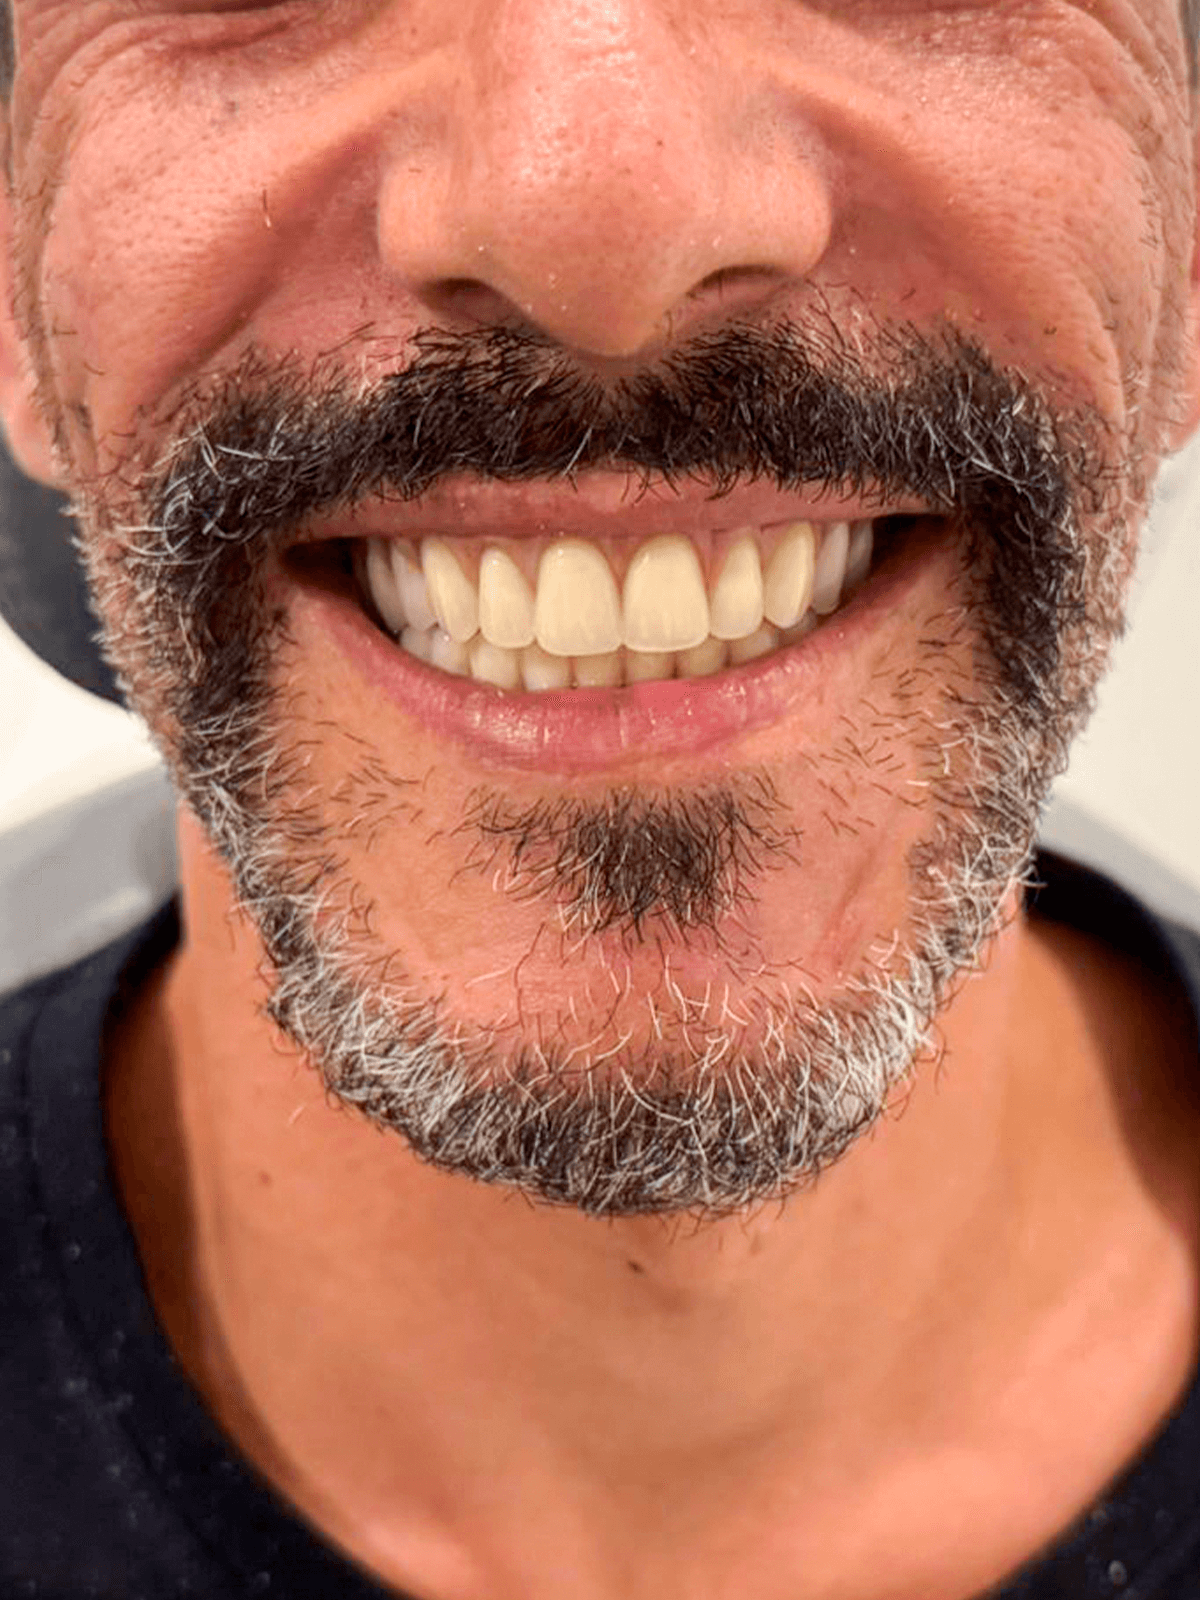

Próteses dentais

O caminho para um sorriso completo e confiante, restaurando sua estética e funcionalidade.

Implante Dentário

A solução permanente e natural para recuperar seus dentes perdidos e sorrir sem preocupações.